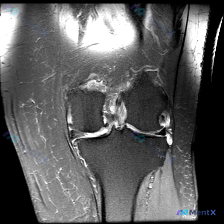

刚看到这张膝关节MRI冠状位T2加权像的读片需求,核心问题是「半月板异常」,整理了完整的影像资料和分析思路跟大家分享。

- 骨骼部分:股骨远端、胫骨近端骨髓信号整体相对均匀,无骨皮质中断或骨质破坏,但股骨髁间窝上方、骨骺端区域骨髓信号欠均匀,不能排除轻微应力性改变或骨髓水肿

- 半月板部分:内侧半月板形态、信号尚可,无明确撕裂信号;外侧半月板形态异常,内部/边缘可见明显T2高信号,提示信号异常

- 韧带部分:本切面交叉韧带走行区信号杂乱,可见水肿/撕裂样高信号,提示韧带结构可能存在损伤

- 关节情况:关节腔内可见明显T2高信号积液影,分布于髁间窝周围及关节侧方,关节囊略显膨隆

核心病变位置:外侧半月板体部信号异常,髁间窝/交叉韧带走行区是最显著的异常区域,存在大片弥漫性T2高信号,边界模糊,提示明显炎性水肿或组织损伤。

- 髁间窝大片T2高信号高度提示前交叉韧带损伤,这是最核心的病变

- 外侧半月板信号异常常是ACL损伤的合并损伤

- 明显关节积液是创伤后典型继发反应

- 股骨骨髓信号异常可以用伴随骨挫伤/应力性改变解释

结合目前单张影像的信息,最符合的判断是:急性创伤性膝关节损伤,以交叉韧带区域损伤为核心,合并外侧半月板损伤倾向、膝关节积液,不能排除伴随骨挫伤。